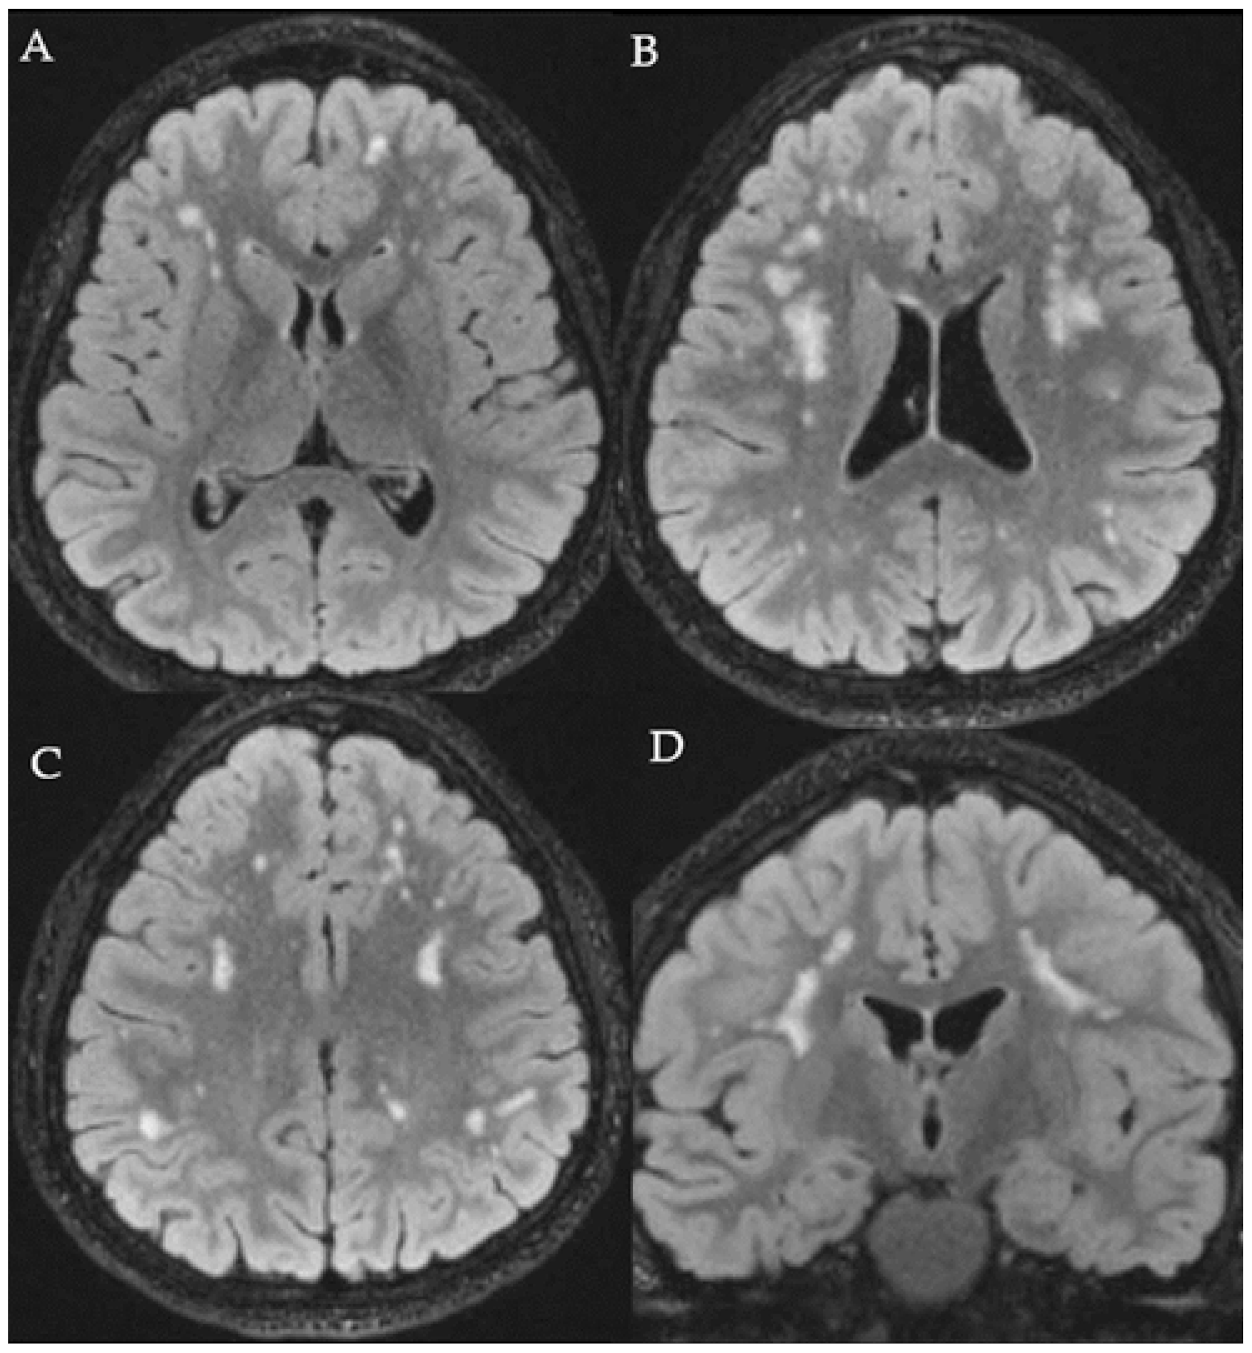

3.2. Instrumental Examination